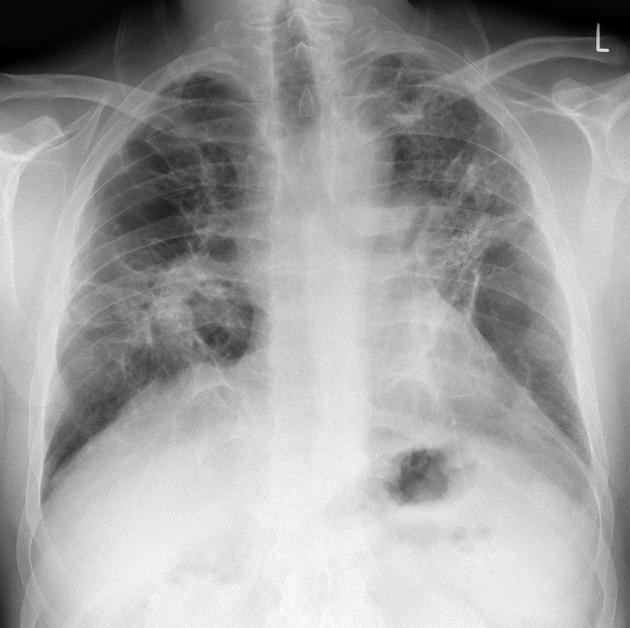

Image radiologique PA

d'une fibrose pulmonaire avec aspect de fibrose de

articulaire sterno-claviculaire gauche d'une

spondilite ankylosant |